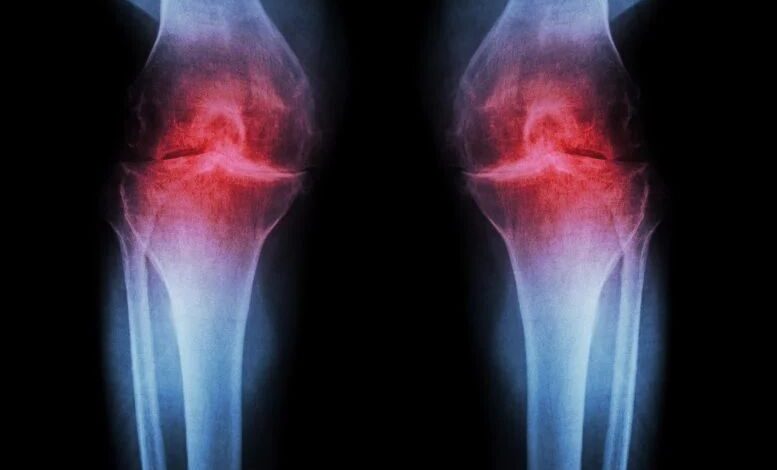

بیشتر بخوانید »تهران- مگ زیبا- دانشمندان با کشف یک روش درمانی انقلابی اعلام کردند بهزودی میتوان غضروف فرسوده زانو را با یک…